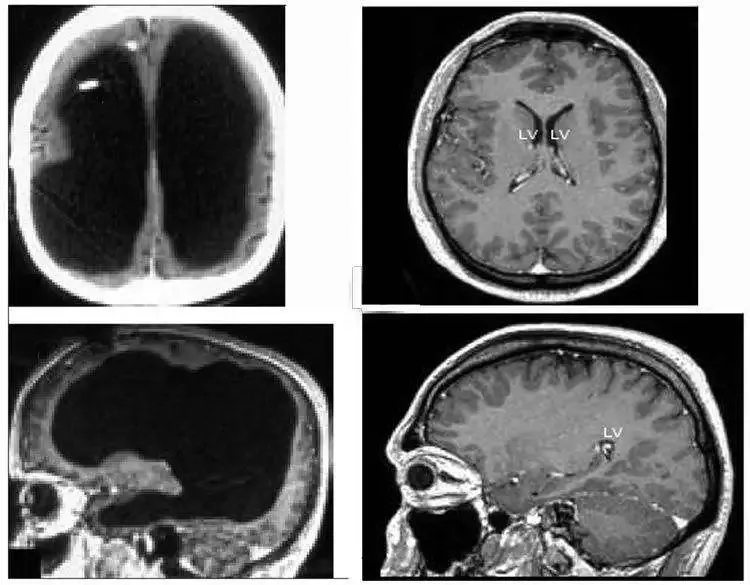

《柳叶刀》曾在2007发布过这样一个案例:一名44岁的法国男子左腿有点问题,他就找人看,顺便对大脑做了核磁共振扫描,结果发现他的脑里都是积水,脑组织已经被挤得只剩下薄薄的一层。和正常人相比,他的大脑“几乎不存在”。经过测试,他的智商有75,和阿甘差不多。他很早就结了婚,还生了两个孩子,生活很美满,可以说没受到什么影响。如果不是因为左腿疼,他可能永远也不会发现自己其实“没脑子”。

左边是该男子的大脑;右边是正常人的大脑。中间黑色部分就是积水